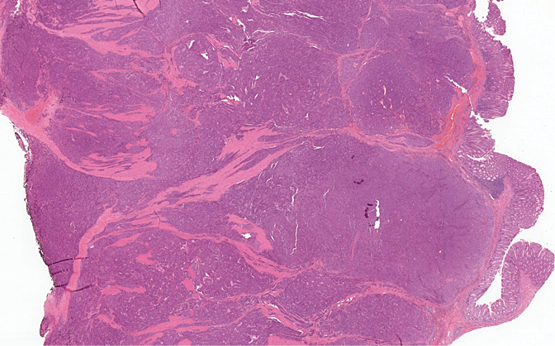

1 pav. Visą storosios žarnos sieną stambiais solidiniais mazgais infiltruojantis navikas (HE 10X)

Mikroskopiniuose preparatuose (1 pav.) matyti infiltratyviai žarnoje plintantis navikas, sudarytas iš trabekulinų, lizdinių ir solidinių struktūrų su pavieniais likutiniais spindžiais, kurias formuoja mišri ląstelių populiacija (2 pav.): dominuoja epitelioidinės kohezyvios ląstelės (apie 40 proc. naviko), pasižyminčios negausia ir vidutinio gausumo eozinofiliška citoplazma, smulkaus ir stambesnio kalibro centruotais, ovaliais arba nelygaus kontūro, polimorfiškais branduoliais. Šeivinės ląstelės sudaro apie 30 proc. naviko, ląstelių citoplazma vidutinio gausumo, eozinofiliška, ląstelėse ištęsti vidutinio kalibro branduoliai. Likusią dalį (apie 30 proc. naviko) sudaro diskohezyvios rabdoidinės išvaizdos ląstelės periferizuotais branduoliais ir ryškiomis nukleolėmis, ekscentriška citoplazma ir eozinofiliniais intracitoplazminiais inkliuzais. Matyti gausios mitozės (40/2 mm2), nekrozės iki 10 proc. naviko tūrio, granuliacinis audinys išopėjusiame paviršiuje. Identifikuotas perineurinis naviko plitimas ir intravaskulinė (smulkių šakų ir intraveninė) invazija; naviko struktūros siekė cirkuliarų rezekcijos kraštą. Antrąjį židinį formavo analogiškos to paties naviko struktūros su negausiu likutiniu limfoidiniu audiniu periferijoje (tikėtina metastazė pasaito limfmazgyje, ekstranodaliai plintanti į žarnos sieną).